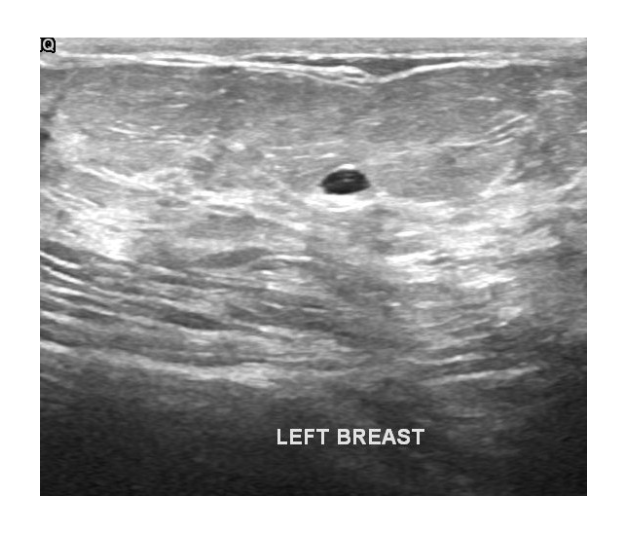

Supports multi-modal inputs including structured indicators, voice, dialogue, and imaging for comprehensive care.